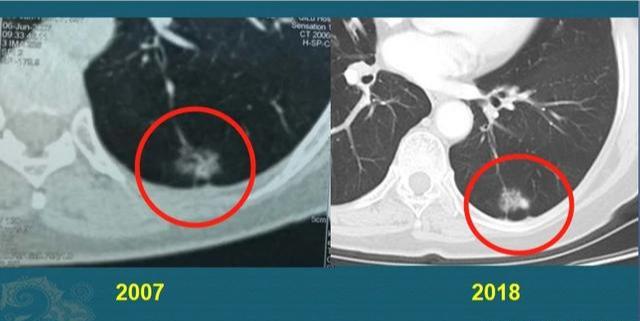

有些肿瘤属于惰性病灶(这种比较少见),癌细胞在较长一段时期内呈惰性进展,像动物冬眠一样,甚至十几年保持接近静止的状态。比如下面这个肺腺癌病例:

这位中年女士,体检发现左侧肺腺癌,表现为混合 磨 玻璃结节,形态不规则,伴有胸膜牵拉,肺门侧可见一支供血血管。她对手术非常恐惧,选择密切观察,很幸运,她的这个病灶非常懒,一直到11年后才发现增大迹象,表现为密度增加,实在不敢再拖了,最终手术切除,治愈!